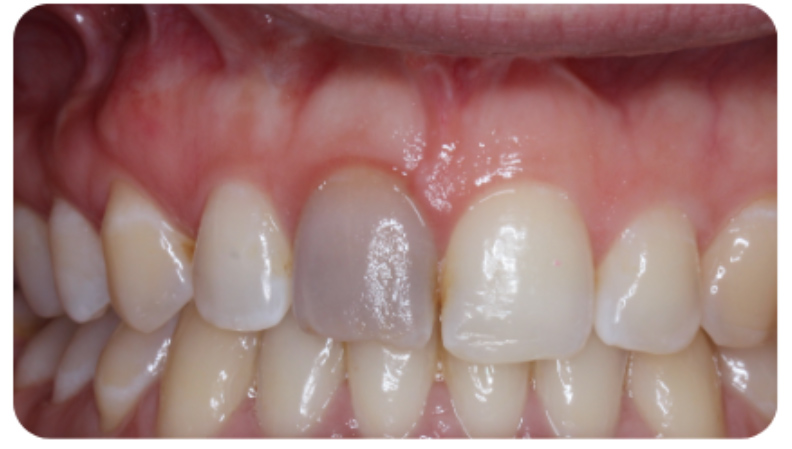

We can treat the yellow discolouration by external tooth whitening. But it may take longer to achieve a satisfactory result. A veneer might be necessary if a satisfactory result cannot be achieved with external whitening alone (Figure 1).

Figure 1: Pulp canal obliteration (PCO). The patient had trauma to UL1 15 years ago and developed a yellow discolouration over time. She was keen to improve the appearance of the tooth. The UL1 was asymptomatic and did not respond to sensibility testing.

Radiographically, UL1 had a normal PDL width and an intact lamina dura could be seen around the tooth. A diagnosis of pulp canal obliteration was reached for UL1. There was no endodontic infection and the patient was advised to have external tooth whitening; this will take longer and a veneer might be necessary if a satisfactory result can’t be achieved with external whitening alone. Figure 1a: Preoperative photograph. Figure 1b: Preoperative radiograph.